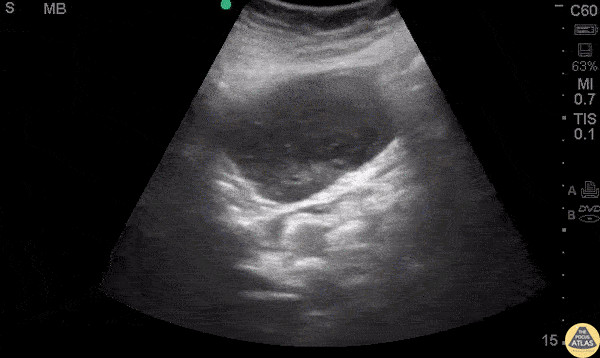

Gastrointestinal Stromal Tumor (GIST) 58 y/o F no PMH with epigastric pain for two days, nausea and generalized weakness but no other symptoms. Vital signs were normal and physical exam was limited due to obesity but revealed moderate tenderness in the epigastric region without distention or peritoneal signs. The remainder of the exam was unremarkable and POCUS was performed. A subcostal view is above showing an undefined hypoechoic, heterogeneous, cystic mass. It was non-compressible with well defined borders. Computed tomography (CT) of the abdomen and pelvis confirmed a large, heterogeneous mass adjacent to the stomach with a small amount of intra-abdominal and intra-pelvic blood. The patient was admitted to general surgery, and endoscopic ultrasonography with biopsy revealed a spindle cell lesion consistent with gastrointestinal stromal tumor (GIST). Gastrointestinal stromal tumors are the most common mesenchymal tumors of the GI tract with an incidence of 14 to 20 cases per million.(1) They can be located anywhere in the GI tract but are most frequently identified in the stomach (50-60%) and small bowel (30-40%).(2) Symptoms include abdominal pain, nausea, dyspepsia, fatigue, constipation, or diarrhea. Gastrointestinal stromal tumors have varying appearance on different imaging modalities and are often first seen on abdominal ultrasonography.(3) A subcostal view is be a good place to begin POCUS, considering that most GISTs are located adjacent to or within the stomach. Case reports describe the diagnosis of GIST with help of initial transabdominal ultrasonography.(4,5) Appearance on ultrasonography may vary, depending on size and mitotic activity.(3) Larger tumors may often appear as heterogeneous masses, filling the abdomen with hypoechoic areas consistent with necrosis.(1) However, reports also describe tumors initially seen as extraluminal hypoechoic masses of varying size.(5) While transabdominal ultrasonography is an excellent starting point, CT ultimately shows better detail for staging and characterization. Endoscopic ultrasonography can be used for further definition and ultimately for diagnosis, as biopsy is required. Point-of-care ultrasonography may be an excellent tool for determining further management of patients with non-specific abdominal symptoms. While you may not initially suspect a GIST when starting your POCUS, an unidentifiable mass in the GI tract should prompt further investigation, which can ultimately lead to formal diagnosis. References Vernuccio F, Taibbi A, Piccone D, et al. Imaging of Gastrointestinal Stromal Tumors: From Diagnosis to Evaluation of Therapeutic Response. Anticancer Research 2016;36(6):2639–48. Wronski M, Cebulski W, Slodkowski M, Krasnodebski I. Gastrointestinal Stromal Tumors . Journal of Ultrasound 2009;28(7):941–8. King DM. The radiology of gastrointestinal stromal tumours (GIST). Cancer Imaging 2005;5(1):150–6. Sugihara T, Koda M, Tanimura T, Yoshida M, Muruwaki Y. A report of three cases of exophytic gastrointestinal stromal tumor detected by transabdominal ultrasound. Journal of Medical Ultrasonics 2016;43(1):107–11. Chan KP. What’s the Mass? The Gist of Point-of-care Ultrasound in Gastrointestinal Stromal Tumors. Clinical Cases and Reports in EM 2018;2(1).